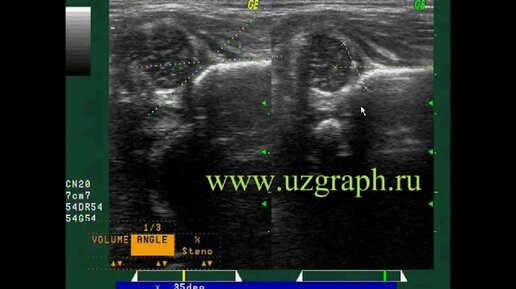

Измерение угла на снимках УЗИ онлайн на ActionScript

Для врачей УЗИ